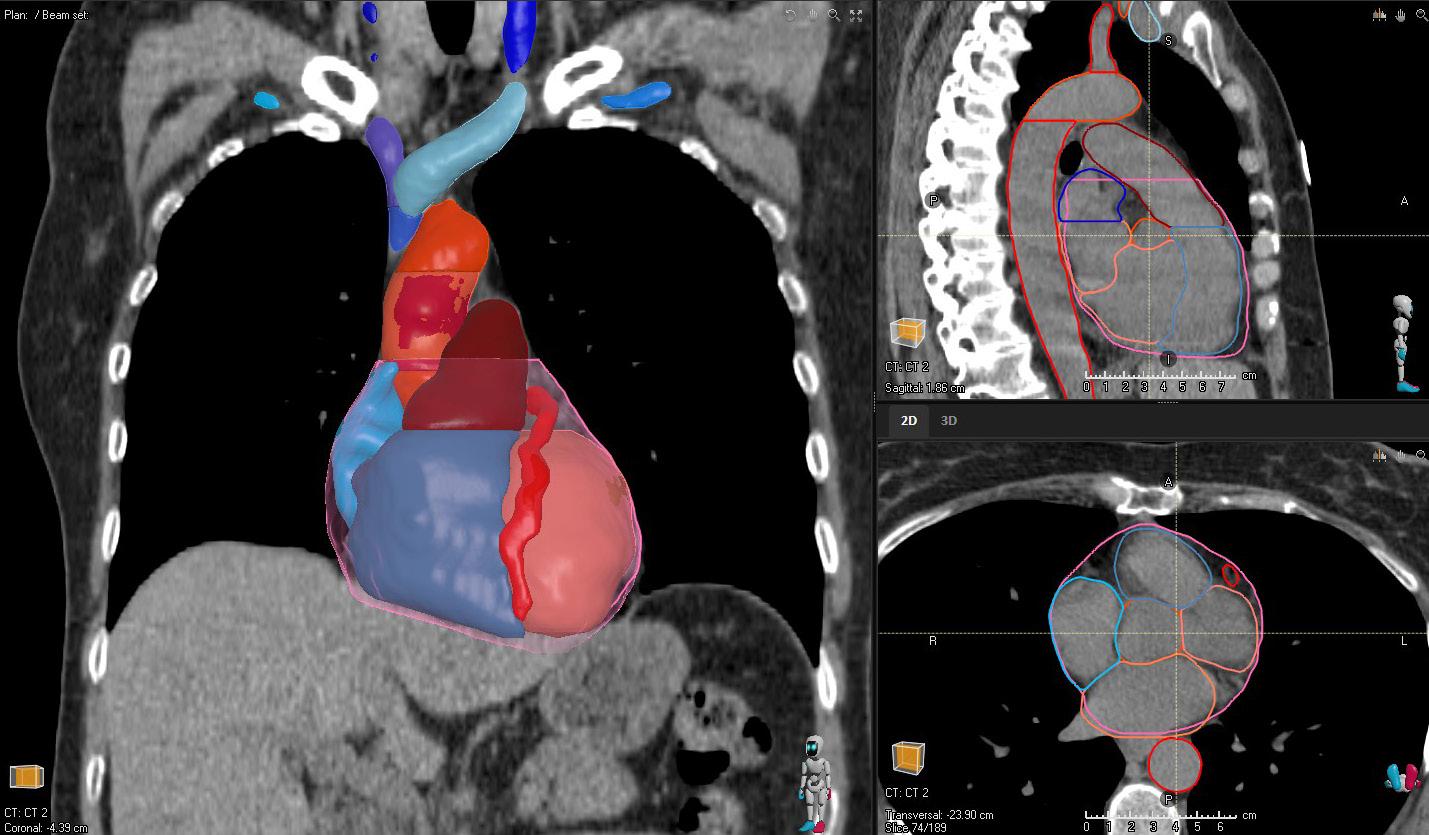

HEART SUBSTRUCTURES

STRUCTURES

A_Aorta_Asc_Prox NEW

A_Aorta_Root NEW

A_LAD

A_Pulmonary NEW

Atrium_L NEW

Atrium_R NEW

V_Pulmonary NEW

V_Venacava_S_Prox NEW

Ventricle_L NEW

Ventricle_R NEW